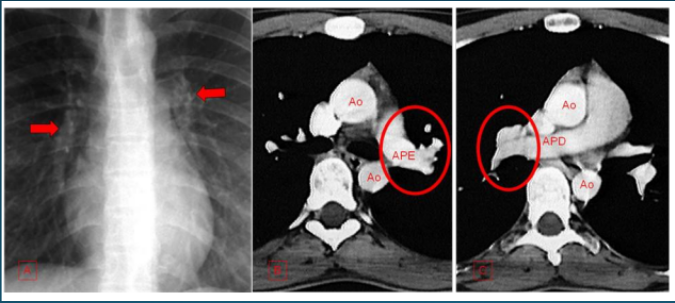

Outras condições: Além dessas, a TC do tórax também é útil para investigar embolia pulmonar, doenças da pleura, aneurismas da aorta, entre outras patologias.

A compreensão da anatomia torácica é fundamental para a interpretação adequada das imagens de TC.

Espaço entre os pulmões contendo coração, grandes vasos, esôfago e traqueia